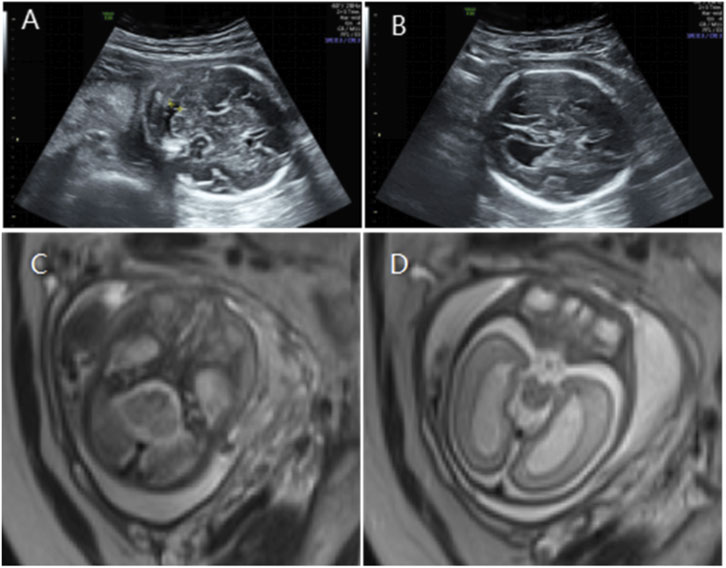

Ultrasound and MRI scans labeled A to D depict different views of a fetal head and brain. Images A and B show ultrasound scans with distinct circular shapes, potentially representing cranial structures. Images C and D are MRI scans presenting different levels of detail and contrast, emphasizing varying tissue densities in the fetal brain.

Figure 2. (A) Transverse ultrasound section showing the fetal cerebellum with a transverse cerebellar diameter of 27.8 mm (<–3.0 SD for gestational age). (B) Axial ultrasound view in thetransventricular plane demonstrating bilateral ventriculomegaly with atrial widths of 12.3 mm (left) and 12.5 mm (right). (C,D) Axial T2-weighted fetal MRI confirming reduced cerebellar size and bilateral ventriculomegaly.